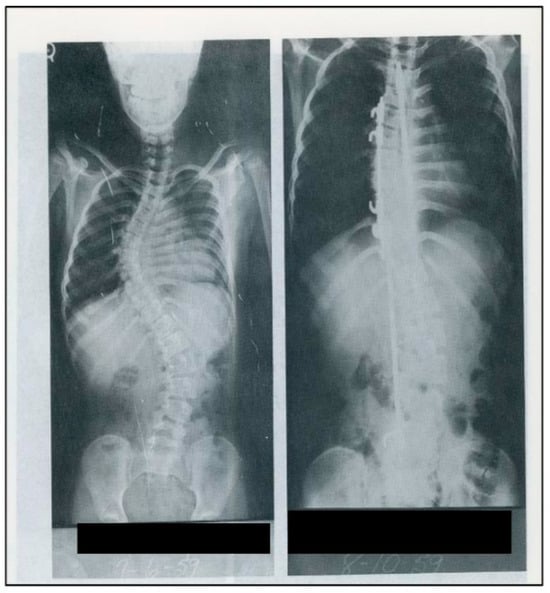

Figure 6. Pre- and post-operative radiographs of a 12-year-old scoliotic patient of Harrington’s after internal fixation with Harrington instrumentation, 1959 (Used with permission from the Harrington Archives, Department of History and Philosophy of Medicine, University of Kansas Medical Center).